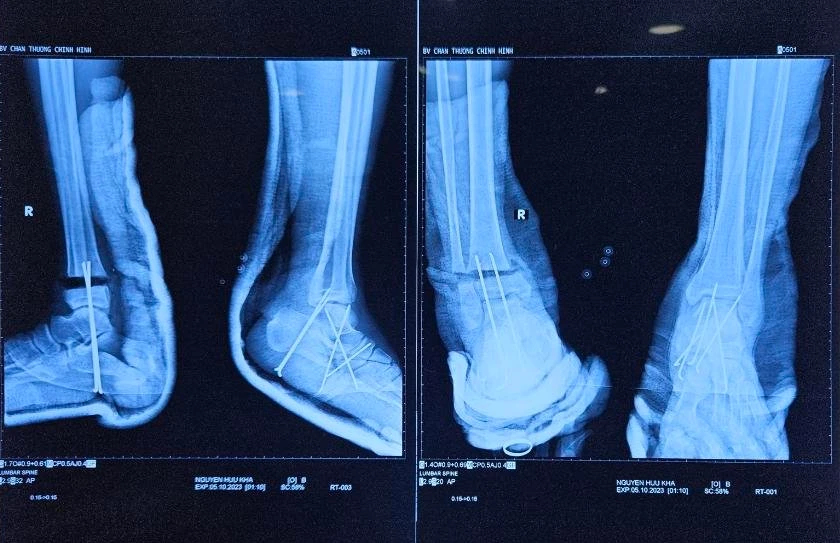

Hai cổ chân gần đứt lìa sau phẫu thuật đã ổn định. Ảnh: BVCC

Ông K được hồi sức trước và trong lúc mổ. Trong quá trình mổ, BS cắt lọc, xuyên đinh cố định khớp cổ chân phải, nối vi phẫu động mạch chày sau và hai tĩnh mạch tùy hành.

Sau đó, BS khâu vết thương, nẹp bột cẳng bàn chân phải. Tiếp theo, BS cắt lọc, xuyên đinh cố định khớp cổ chân trái, khâu nối bó mạch thần kinh chày sau, khâu vết thương, nẹp bột cẳng bàn chân trái.

Hiện hai cổ chân gần đứt lìa của ông K cải thiện tốt.